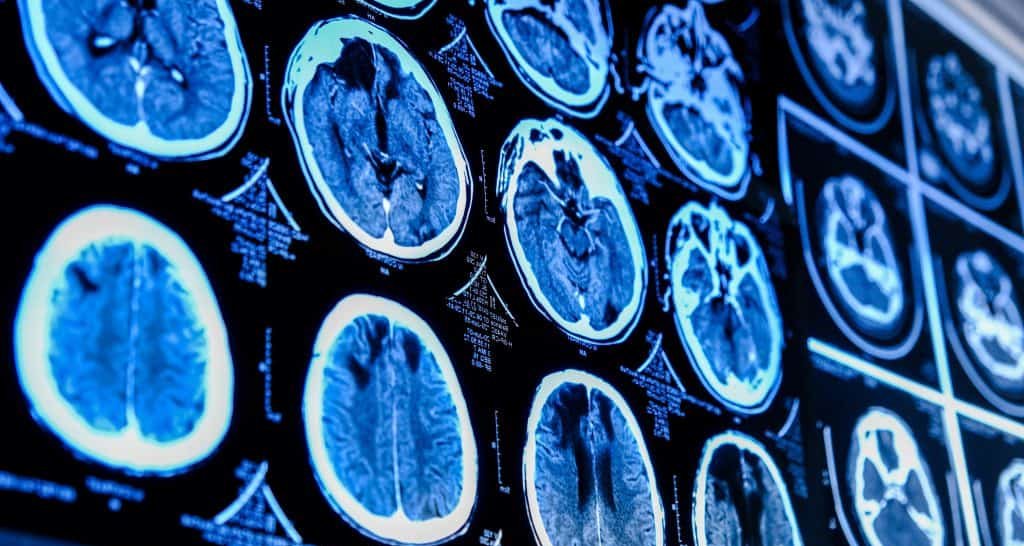

São Paulo, 27 de novembro de 2025 – Pesquisadores da Universidade de Sevilha, na Espanha, descreveram com precisão as regiões cerebrais que parecem funcionar como epicentros das primeiras alterações estruturais em pessoas com transtornos do espectro da esquizofrenia (TEE). O trabalho, publicado na revista Nature Communications, examinou imagens de ressonância magnética de mais de 500 voluntários e identificou queda acentuada na semelhança morfológica entre áreas dos lobos temporal, cingulado e insular, locais fundamentais para o processamento cognitivo e emocional.

Para quantificar mudanças microscópicas na arquitetura do cérebro, os cientistas recorreram às chamadas redes de Divergência Inversa Morfométrica (sigla em inglês: MIND). O método calcula o grau de semelhança entre diferentes regiões a partir de características como espessura cortical, área de superfície e volume. Quanto menor o valor de MIND, menor a correspondência estrutural e maior a evidência de desconexão anatômica entre as áreas avaliadas.

A novidade do trabalho espanhol está em delimitar precisamente quais regiões sofrem danos antes das demais. Segundo os autores, temporal superior, giro cingulado e ínsula exibem as maiores quedas de similaridade estrutural logo no início do transtorno. Essas áreas, classificadas como associativas de ordem superior, amadurecem mais tarde no desenvolvimento humano e são cruciais para funções cognitivas complexas, como integração sensorial, tomada de decisão e regulação emocional.